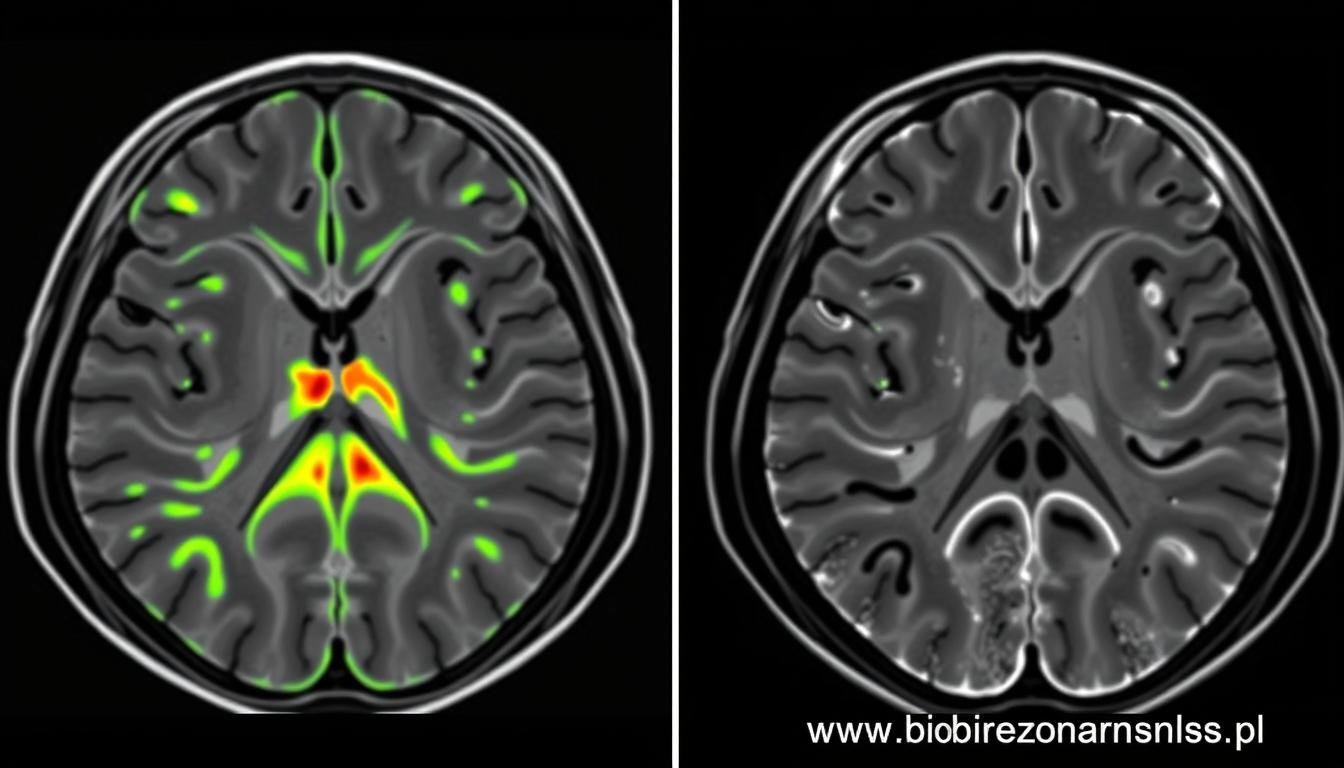

Stwardnienie rozsiane (SM) to przewlekła choroba autoimmunologiczna, w której układ odpornościowy atakuje osłonki mielinowe neuronów. Wczesna diagnostyka ma kluczowe znaczenie dla skutecznego leczenia. Biorezonans NLS umożliwia wykrycie subtelnych zmian w strukturze mieliny, zanim staną się one widoczne w badaniach MRI.

Pacjent, 58 lat, zgłosił się z niespecyficznymi objawami: okresowym drżeniem rąk i niewielkimi zaburzeniami równowagi. Konwencjonalne badania neurologiczne nie wykazały jednoznacznych nieprawidłowości. Badanie Biorezonansem NLS ujawniło subtelne zmiany w funkcjonowaniu jąder podstawy mózgu, charakterystyczne dla wczesnego stadium choroby Parkinsona.

Diagnostyka neurologiczna dysponuje szeregiem metod badawczych, od badania klinicznego po zaawansowane techniki obrazowania. Biorezonans NLS nie zastępuje tych metod, ale stanowi cenne ich uzupełnienie, oferując unikalne możliwości diagnostyczne.

| MRI (rezonans magnetyczny) | Obrazowanie struktury tkanek za pomocą pola magnetycznego | Wysoka rozdzielczość obrazu, dobra wizualizacja tkanek miękkich | Wysoki koszt, długi czas badania, przeciwwskazania (implanty metalowe) | Biorezonans NLS może wykryć zmiany funkcjonalne przed pojawieniem się zmian strukturalnych widocznych w MRI |

| PET (pozytonowa tomografia emisyjna) | Obrazowanie metabolizmu tkanek | Ocena funkcjonalna, wykrywanie zmian metabolicznych | Wysoki koszt, ograniczona dostępność, ekspozycja na promieniowanie | Biorezonans NLS oferuje podobne informacje funkcjonalne bez narażenia na promieniowanie |

Oprócz funkcji diagnostycznych, technologia Biorezonans NLS oferuje również możliwości terapeutyczne. Bazując na zasadzie biorezonansu, urządzenie może emitować fale elektromagnetyczne o częstotliwościach, które harmonizują z naturalnymi częstotliwościami zdrowych tkanek, wspierając procesy samoregulacji organizmu.

Terapia Biorezonansem NLS opiera się na założeniu, że każda komórka i tkanka w organizmie posiada swoją charakterystyczną częstotliwość drgań. W stanie choroby częstotliwości te ulegają zaburzeniu. Urządzenie emituje fale o częstotliwościach, które wspierają powrót do prawidłowych wzorców drgań, stymulując naturalne procesy regeneracyjne.